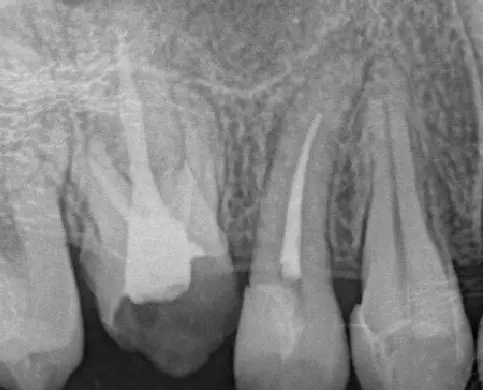

BEFORE

AFTER

治療前

治療後

半年後

※ファイル破折除去の症例です。治療回数はファイル破折除去、被せ物治療まで含めての回数です。

昔の治療で使ったファイルという器具が根っこの先に残ってると言われました。それを除去してもらうのが無理ということで何軒か医院に伺いました。その中ですが歯科さんが説明をしっかりしてくれたので、治療していただくことにしました。結果は見事、器具を除去していただきました。その後、根管治療もうまくできたとおっしゃっていただきました。本当に嬉しいです。ありがとうございます。

副作用・リスク